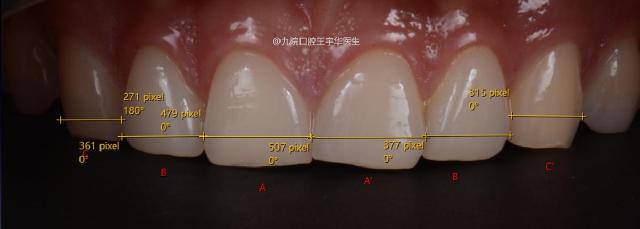

C/B=0.84 B/A=0.78 B’/A’=0.77 C’/B’=0.96

CW/LIW LIW/CIW ⽐值偏⼤ 11 21⽛间隙较⼤影响美感